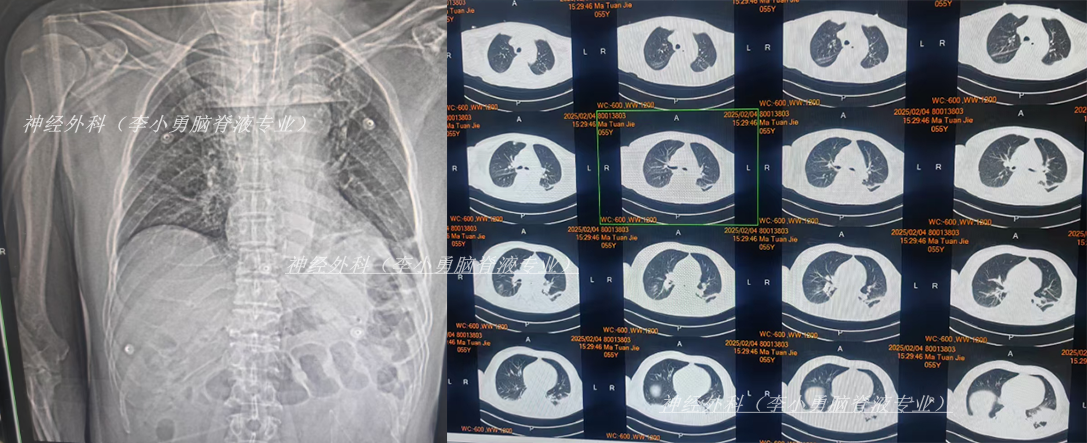

治疗4天后即2025年1月13日,仍发热,查头颅CT(图-7)和肺部CT(图-8)后继续抗感染治疗。

图-7:2025年1月13日头颅CT

图-8:2025年1月13日肺部CT

保守治疗1周没有效果,于2025年1月18日(颅骨修补术后93天即脑室腹腔分流术后121天),再次选择了北京另一所三甲医院,查头颅CT(图-9)后急诊留观,行脑脊液检查提示人类疱疹病毒。

入院当天查头颅CT示颅脑术后改变,脑室扩张,双侧额部硬膜下积液(图-12);胸部CT示两肺炎性病变,心包积液,双侧胸腔积液(图-13)。

图-12:2025年2月4日头颅CT

图-13:2025年2月4日胸部CT